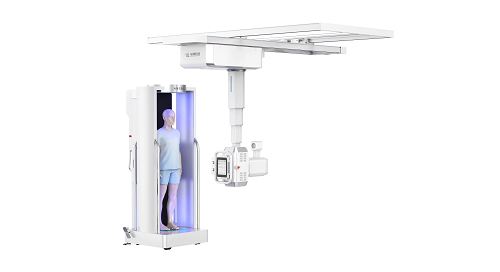

WR-3D即负重位三维影像重建系统,拥有多项发明专利,它不同于常规CT的重建系统,保留DR设备原有形态及操作流程,相比3D机械臂对患者及医生具有更高的安全性;同时在病人旋转床板上加入定位丝结构,创新性地解决了站台旋转过程中导致的患者站立不稳等问题,能通过实时几何校准软件,无需像CT一样需要定期用校准模体对设备进行校准,工作更加快捷高效。并且WR-3D采用了模拟太空舱环抱式设计,搭配360度旋转且可移动的站台,可实现负重位(自然站立状态下)的大幅面自动旋转扫描,能够真实的反映出自然负重位状态下的关节间隙、主要骨骼受力变形及关节的改变情况,在自然负重位状态下对患者被扫描部位进行三维断层扫描及重建。